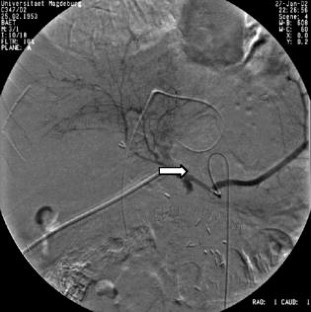

Wir berichten über das diagnostische und therapeutische Vorgehen anhand von 7 Patienten mit Blutungen aus der A. gastroduodenalis (n=5) nach pankreaschirurgischen Interventionen bei Pankreaskopfkarzinom, Rezidiv eines Liposarkoms und chronischer Pankreatitis, der A. hepatica communis (n=1) bei chronischer Pankreatitis und der A. mesenterica superior (n=1) nach akuter Pankreatitis. Anhand von 4 Kasuistiken werden unsere Erfahrungen mit der Implantation von Stentgrafts (Hemobahn®-Prothesen) vermittelt. Den Vorteil der Stentgrafts sehen wir in der sofortigen Blutstillung bei fehlendem Kontakt der Endoprothese zu infiziertem Gewebe und Erhalt der Perfusion des abhängigen Organs. Unsere positiven Erfahrungen mit diesen interventionellen Therapieverfahren erfordern jedoch weitere klinische Untersuchungen, wobei im Mittelpunkt die Indikationen, die technische Erfolgsrate, die stentbedingten Komplikationen und die Langzeitverläufe stehen sollten.

Spontaneous or postoperative hemorrhage into the abdominal cavity due to inflammatory vessel arrosion represents an uncommon but menacing situation. According to the literature, such hemorrhage is associated with a lethality of nearly 2%. Therapeutical options include reoperation and interventional radiological techniques such as endovascular catheter techniques with stent graft implantation or the embolization of vessels. We report on the management of seven cases with hemorrhage either from the gastroduodenal artery (n=5) following pancreatic surgery for pancreatic carcinoma, liposarcoma, and chronic pancreatitis or from the common hepatic artery (n=1) and the superior mesenteric artery (n=1) following chronic pancreatitis. The present article describes our experiences with stent graft implantation (hemobahn prosthesis) in four cases. Based on these experiences, we see the advantages of stent grafts in primary hemostasis without any contact to infected tissue and the preservation of regular perfusion. However, further clinical data are required focussing on indication, technical success rates, stent-related complications, and long-term outcome.

Abb. 4